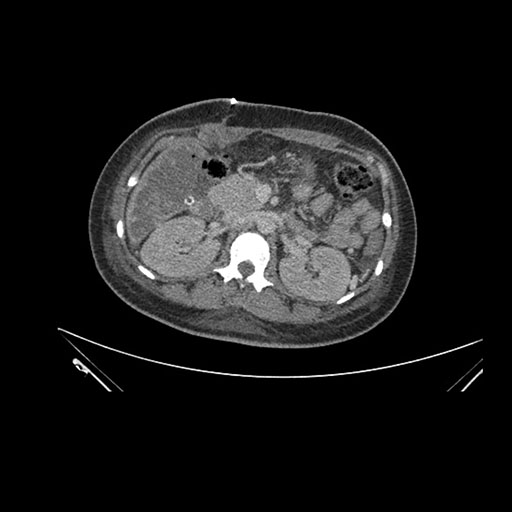

Axial Arterial

Imaging analysis

Based on initial findings, which issue(s) would you be most concerned about?